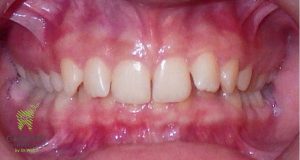

Initial and Final photos correcting a deep bite